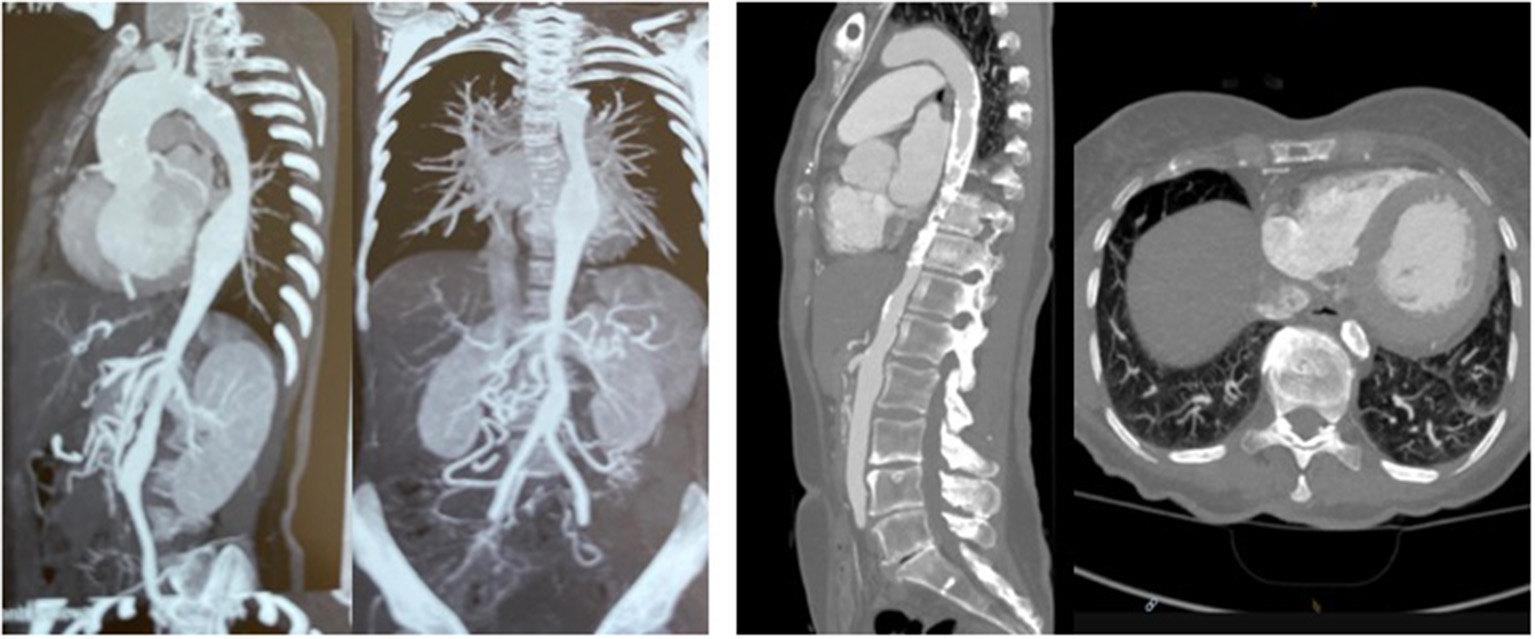

The first patient is a 15–20 year-old female who suffered from increasing claudication symptoms that appeared after a walking distance of <50–100 meters. Suspicion of Takayasu arteriitis was made in the past and clinical examination revealed arterial hypertension of the upper extremities but no pulse at the femoral arteries and distally of them. CT-scan with angiography showed several narrowing at the level of the descending thoracic but also of the abdominal aorta (Figure 13 both left). Since the contrast agent seemed to stop at the level of the external iliac arteries, a direct angiography was planned but the catheter could not be introduced, neither into the radial nor into the femoral arteries for selective injections. At that stage we recommended an extra-anatomic (subcutaneous) thoraco-bifemoral bifurcated graft and this procedure will be performed as soon as possible.

Figure 13

Left (2 pictures): CT-angiogram of a young patient with Takayasu aortitis with multiple stenoses in the thoracic and abdominal aorta and occlusion of the iliac arteries scheduled for an descending to bi-iliac extra-anatomic bypass. Right (2 pictures): CT-angiogram of a 45 yr-old female with severe calcific narrowing of the descending aorta as a result of a Takayasu more than 25 years before. Endovascular procedure was thought to be not ideal in this case.

The second patient is a 45-year old female known for a Takayasu arteriitis who suffered from drug-resistant arterial hypertension, renal failure and symptoms of claudication Fontaine stage IIb-III with a walking distance of <100 m and sometimes pains at rest. She presented with a localized severe calcific stenosis of the descending aorta with a resting lumen of 3–4 mm at the narrowest site (Figure 13 both right). She was originally referred for evaluation of an endovascular approach but the interventional radiologist denied this possibility. Finally, she received an extra-anatomic ascending-to-infrarenal aortic bypass. A 16 mm vascular graft was anastomosed on the beating heart at the right lateral level of the tangentially clamped ascending aorta. The graft was then brought to the right close to the right atrium and passed through the diaphragm, then through the bursa omentalis to the retroperitoneum and the infrarenal aorta where the distal anastomosis was constructed approximatively 4–5 cm above the aorto-iliac bifurcation. Postoperative course was uneventful and symptoms as well as the arterial hypertension greatly improved soon after surgery. CT-scan demonstrated the correct position of the extra-anatomic graft (Figure 14).

Figure 14

Postoperative 3-D reconstruction of the CT-angio following ascending to infrarenal bypass in the patient with very calcified and narrowed descending aorta following Takayasu disease.